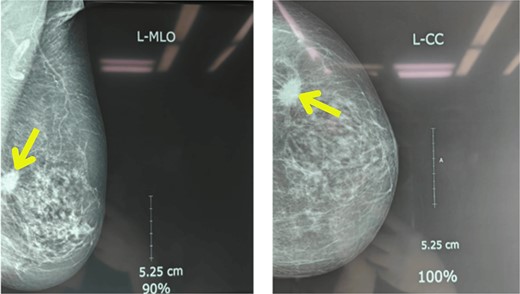

Upon examination, her general condition was fair and vitals were stable. Local examination revealed 3 cm × 3 cm hard, mobile, painless lumps located at 9 o’clock in the right breast 3 cm from Nipple-areolar complex (NAC) and 4 cm × 3.5 cm similar mass at 3 o’clock in the left breast. The axillary and supraclavicular lymph nodes were not palpable. There was no skin, nipple, or areolar changes. Rest of the systemic examinations were normal. Blood and urine tests were within normal limits. Diagnostic mammography revealed well-defined high-density mass lesions of 3.5 × 3.5 cm with spiculated margins in the upper outer quadrants of both breasts and features suggestive of breast imaging reporting and data system (BIRADS) category 5 (Figs 1 and 2).

Mammography showing well-defined high-density mass lesions of 3.5 × 3.5 cm with spiculated margins in the upper outer quadrants of right breast.